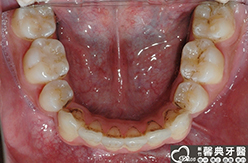

上、下顎前突,俗稱暴牙,由於上下前牙向前暴出,在外觀上容易產生牙齒外露的現象,雙唇較難自然閉合,嘴唇看也來也會比較厚。

患者︰趙同學,20多歲,學生。

主訴︰齒列不正,暴牙,不好看。

治療計劃︰上下顎齒列平整、後縮,重建正常咬合關係。

| ●治療前 | ●治療後 | |